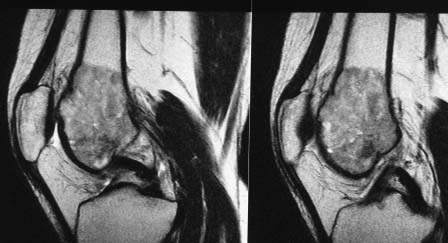

Опухоль дистального метаэпифиза бедренной кости |

Помогите определиться с дальнейшей тактикой у молодой женщины с опухолью дистального отдела бедра. Обратилась на консультацию молодая женщина 34 лет. В январе появились боль в правом коленном суставе. Амбулаторно р- гр в прямой проекции - норма. Была незначительная травма. Боль усилилась. На днях повторно обратилась в поликлинику на рентгенограммах выявлена опухоль дистального метаэпифиза бедренгой кости. Сделано мрт. Мягкотканного компонента нет. Суставной хрящ пока интактен. Рентгенограмм прилагается. Завтра выложу мрт и сделаем ркт ( то же выложу) Предполагаю, что это остеобластокластома. Биопсию не сделаем, кт с контрастом и сцинтиграфию тоже. Учитывая угрозу патологического перелома рекомендовал костыли.

прилагаю МРТ и КТ. Образование накапливает радифармпрепарат :(

Снимки

Внешне похоже на ОБК. Другой вариант - аневризмальная киста, но вряд ли (на МРТ обычно видны множественные уровни жидкости).

Гигантоклеточная опухоль может быть гиперваскулярной, но обычно не в длинных костях.

В любом случае, без биопсии я ничего не делал бы. Это противоречит современным онкологическим принципам.